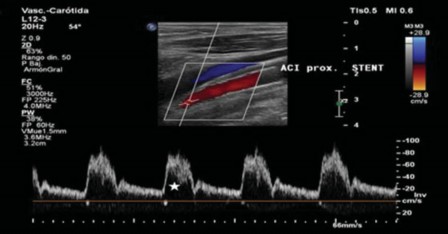

En el caso del stent, el estudio en modo espectral debe ser realizado pre stent, intra stent en su sector proximal, medio y distal y posterior al mismo. Es necesario tomar en cuenta las características morfológicas dela onda. Debido a la laminaridad de los glóbulos rojos en el vaso nativo la onda del Doppler se agrupa en la región superior del espectro, dejando por debajo un área vacía, la cual se denomina ventana espectral (►Fig. 7). El flujo en el interior del stent, en algunos casos, puede perder esa uniformidad por lo que implica una pérdida de la ventana espectral y no significar un hallazgo patológico. Además se puede objetivar ausencia de la ventana espectral en casos de estenosis, a causa del flujo turbulento.

EDC y espectral en la porción media de un stent con ondas de morfología y velocidad normal (estrella, ventana espectral).